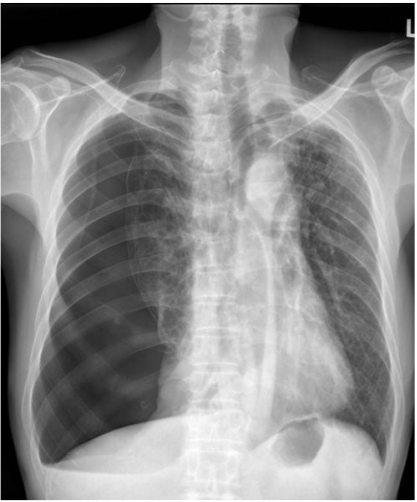

74.61歲男性突發性的胸痛、呼吸困難,其胸部X光如圖示,最主要的診斷為何? (A)肺氣腫 (B)肺挫傷出血 (C)氣胸 (D)肺炎